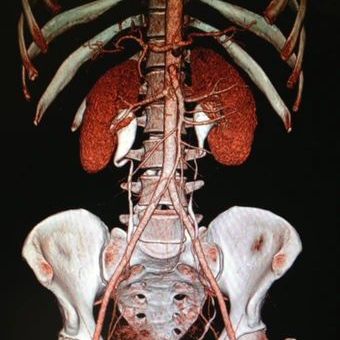

CT ANGIOGRAM

Normal kidney position

The kidneys lie retroperitoneally (behind the peritoneum) in the abdomen, either side of the vertebral column. They typically extend from T12 to L3, although the right kidney is often situated slightly lower due to the presence of the liver. Each kidney is approximately three vertebrae in length.